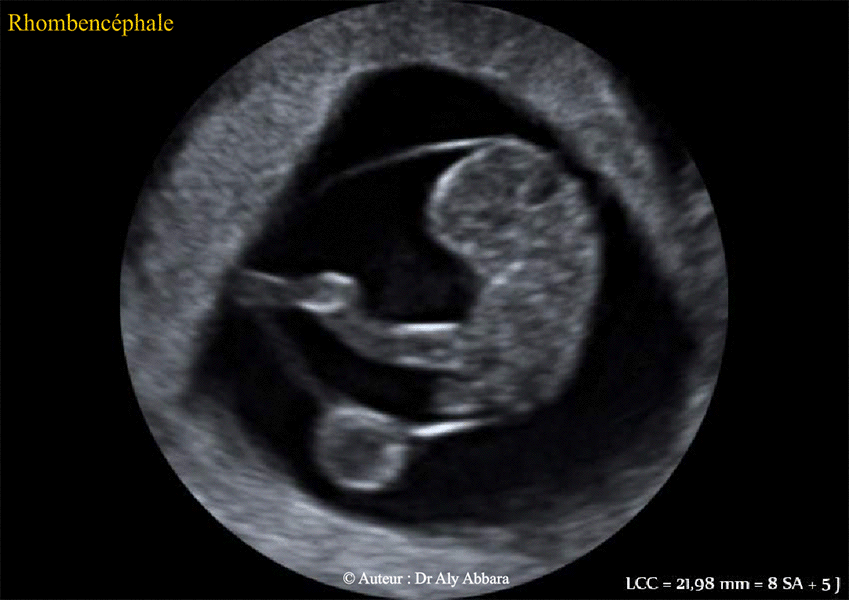

Cerveau embryonnaire - coupe échographique sagittale médiane - embryon âgé de 8 SA + 5 jours :

Analyse des éléments formant la

fosse rhombencéphalique (ou courbure pontique)

et leur futur

développement